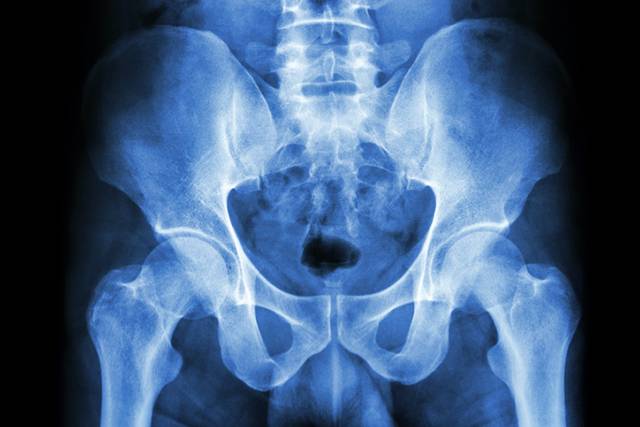

고관절 골절은 수술 환자의 2년 내 사망률이 24%대에 달하는 위험한 질환이다. 고령자의 경우 고관절 골절로 인해 움직임이 제한되면서, 욕창이나 폐렴·심장질환 등 합병증도 나타날 수 있다. 고관절 골절 환자 중 14.8%는 이차성 고관절 골절을 겪기도 한다. 최근에는 고령화와 함께 운동 부족에 따른 근육량 감소·골다공증 악화·관절 퇴행 등으로 인해 고관절 골절 위험이 높아지고 있다. 겨울철 고관절 골절 예방법에 대해 알아본다.

고관절 상단부인 대퇴경부에 골절이 발생하면 인공관절 삽입 수술이 필요하다. 수술 후 3개월부터 대부분 일상생활이 가능해지며, 6개월 후부터는 가벼운 조깅 등 운동도 할 수 있다. 다만 양반다리나 쭈그리고 앉는 자세는 인공 고관절을 이탈시킬 수 있어 주의해야 한다.